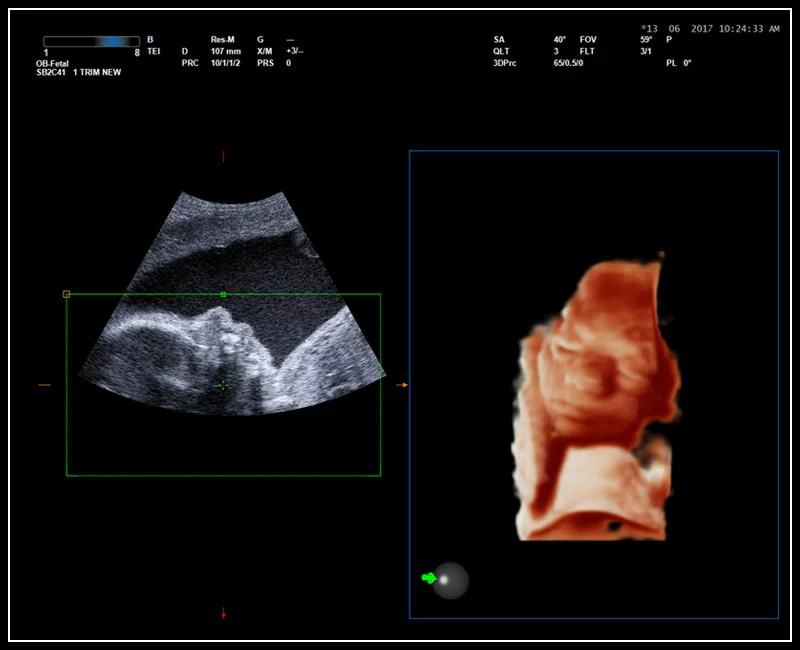

MyLab™9 Platform - Real-time baby face with 4D imaging

MyLab™9 Platform - Real-time baby face with 4D imaging

MyLab™9 Platform - Baby Face rendering in real-time with XLight

MyLab™9 Platform - Baby Face rendering in real-time with XLight